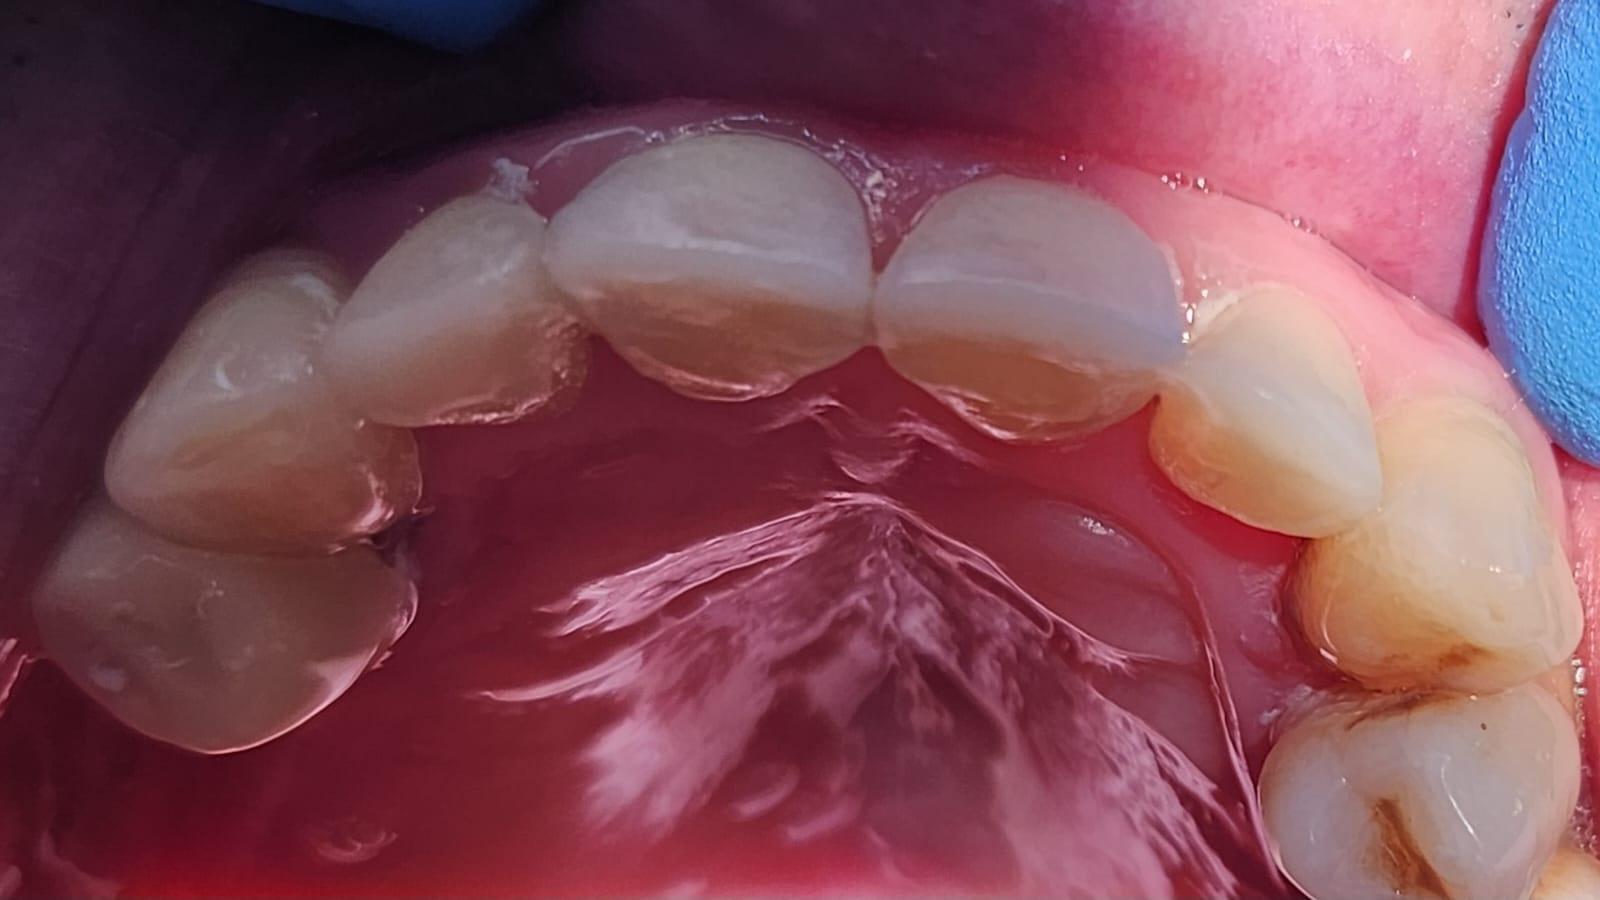

Stresul, fumatul, o igiena dentara precara, dar si modul de alimentatie duc la formarea cariilor. Acestea, netratate, favorizeaza aparitia infectiilor care vor dezvolta chisturi. Astfel de probleme se trateaza cu ajutorul tratamentului endodontic, zona respectiva fiind bine izolata pentru a preveni alte infectii. Atunci cand masurile nu sunt luate din timp, pulpa infectata moare si se formeaza chisturi la nivelul radacinii, iar interventia va deveni mai complexa.

Tratamentul endodontic este mult mai eficient si usor atunci cand bacteriile nu ajung pana in varful radacinii si nu apar chisturile.